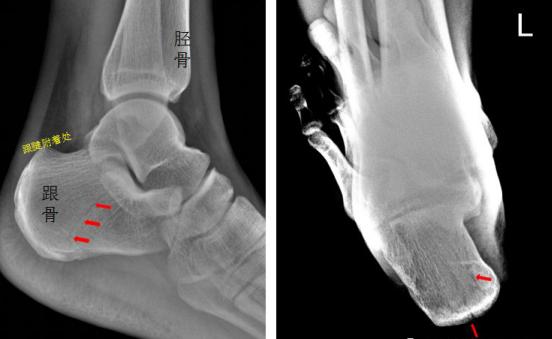

2、患者从二楼房顶坠落,后脚跟着地,拍片如下,

左侧跟骨见骨折透亮线,后缘骨皮质连续中断,左侧跟骨骨折

3、患者脚掌被车轮碾压,拍片如下:

右足斜位示 右侧跟骨前部见骨折透亮线,右跟骨前部骨折。